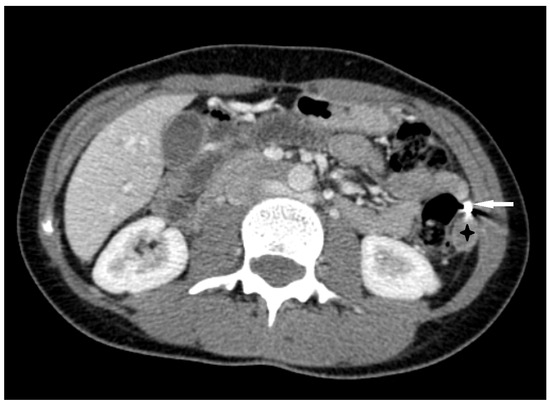

- Hung, N.K.; Ha, D.M.; Khuong, N.H.; Anh, N.N.; Linh, P.T.T.; Anh, H.M.; Hiep, D.V.; Duc, N.M. Splenic ectopic pregnancy: Rare location of ectopic pregnancy, how does it present? Radiol. Case Rep. 2023, 18, 3884–3888. [Google Scholar] [CrossRef] [PubMed]

- Gao, H.; Yuan, T.; Ding, Y.; Lin, X.; Wang, Q.; Dai, L.; Jiang, G.; Chen, J. Primary splenic pregnancy with hemorrhagic shock. Journal of Obstetrics and Gynaecology Research. J. Obstet. Gynaecol. Res. 2017, 43, 1342–1345. [Google Scholar] [CrossRef]